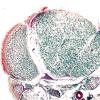

PERIPHERAL NEUROPATHY

18 HEREDITARY DISORDERS

Charcot-Marie-Tooth 1 (CMT-1) (7)